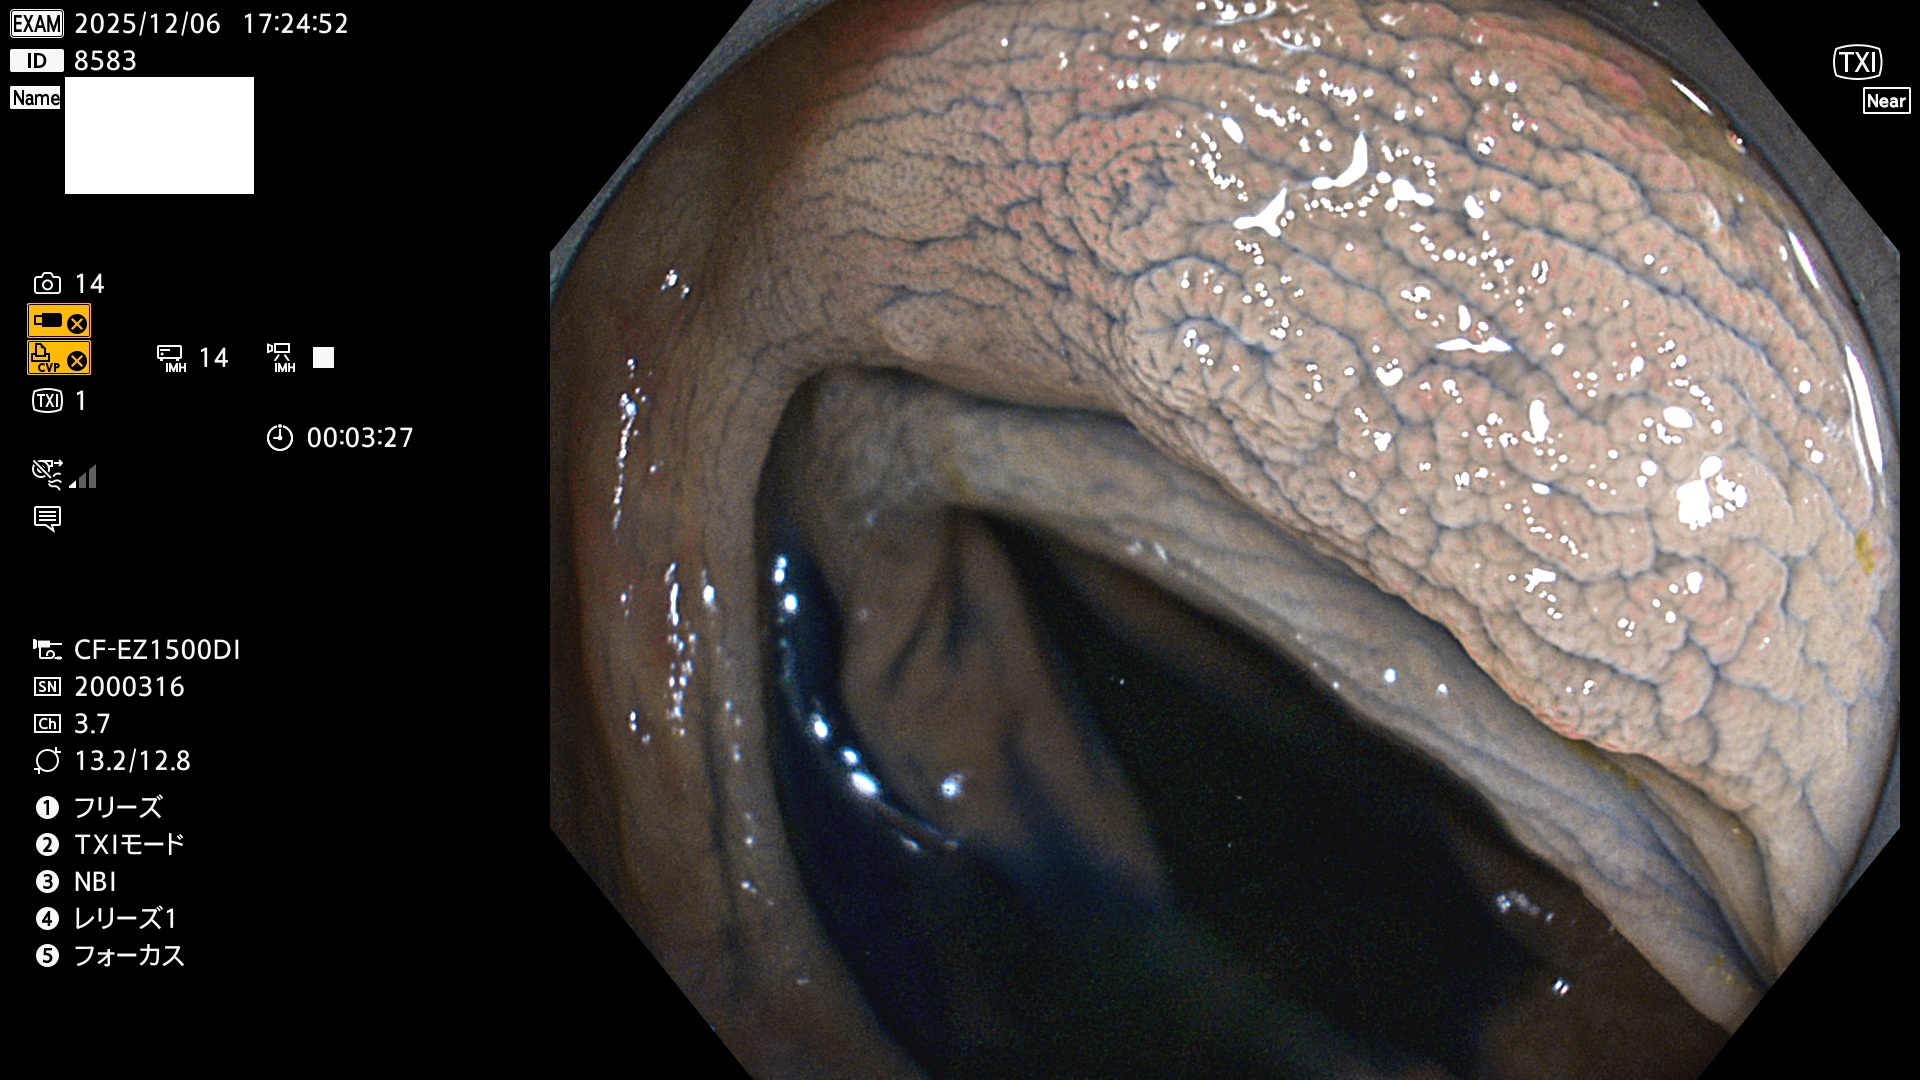

完全に平坦な物をUb、陥凹している物をUcと呼びます。Ubは認識が困難で、Ucはびらん(炎症)と紛らわしいために見落とされやすく、「内視鏡後・大腸癌」の原因になります。

専門的)Uc=De Novo癌? 内視鏡の解像度が低かった時代、このような説もありました。しかし今日の高精度内視鏡では良性の微小なUc型腺腫(APC遺伝子異常の腺腫)が日常的に見つかります。Ucこそが多段階発癌(Adenoma-Carcinoma Sequence)のMain Routeです。

毎週の検査(木・金・土・日)に発見されたUbとUc型・腺腫を、その週の日曜の夜にUPし1週間、提示します。

2025年11月27日〜12月7日の7日間(70件)6個 (Uc_ADR=6個/70人=9%)